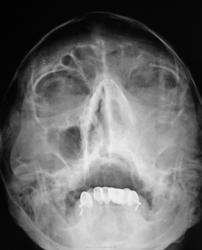

похоже на гиперпластический. В лобной пазухе виден уровень жидкости.

А я плохо вижу костные стенки левой гайм. пазухи...."оно" проростает..

Согласен, невиден медиальный контур левой гайморовой пазухи, надо исключить деструкцию

затемнение не совсем гомогенное, возможно солидные образования в верхнечелюстной пазухе. Во фронтальной не вижу достоверных данных за уровень-что можно было бы трактовать за жидкость. Для этого надо уточнить положение пациента при исследовании, а так же рентгенография пазух лобной кости в боковой проекции в вертикальном положении пациента. Имея только этот снимок - Левостороний гемисинусит. А вообще рекомендовал бы томографию, ну честно-все встало бы на места.

Снимок сделан в вертикальном положении.